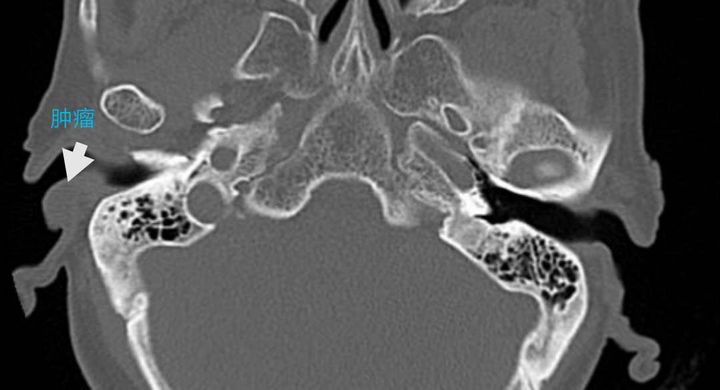

陆奶奶耳里长出黑色肿瘤

考虑陆奶奶年龄偏大,充分完善各项术前准备后,丁主任先取小部分组织作冰冻切片,病理结果报告为:耵聍腺癌。而后在激光辅助下先将肿瘤及周围具一定安全边缘的组织及软骨彻底切除。因肿瘤切除后耳道口缺失范围较大,即取耳前带蒂皮瓣修补创面。手术过程顺利,术后经过精心护理、换药等治疗,陆奶奶现已恢复出院。

据丁吉女主任介绍,耵聍腺肿瘤为外耳道少见疾病,是指发生在外耳道的具有腺样结构的肿瘤,以恶性肿瘤较常见,约占70%。这类肿瘤虽生长缓慢,但易扩展,切除后局部复发率高,晚期可发生远处转移。今年他们已经接诊了两例像陆奶奶这样的患者,其中一例肿瘤已穿透颅骨快长到脑子里。